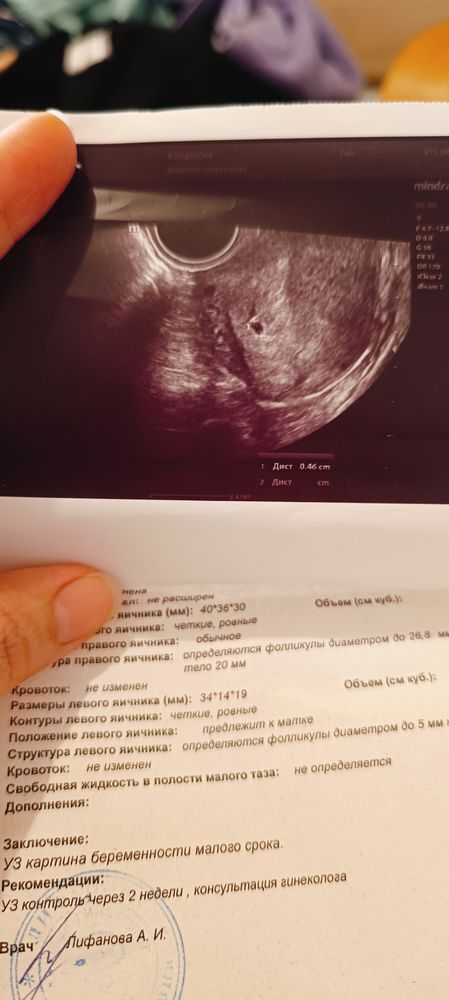

У меня на 16 дпо на УЗИ Изображение

07.09.2024

Эва , вам тоже дали такое фото чудо Изображение

09.09.2024

Дарья, да , но пока очень крошечные, пя 0,18см